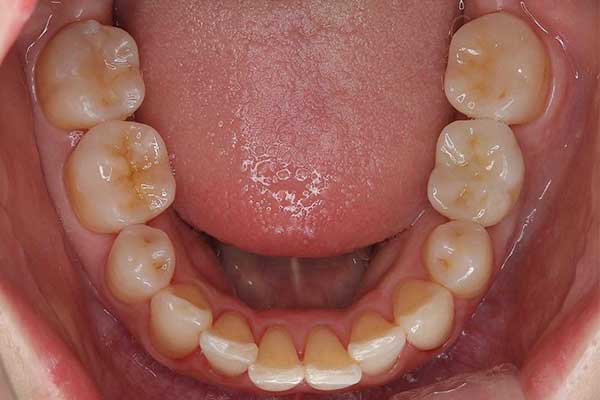

⑩ 詰め物の治療

治療前

治療後

年代・性別

30代・女性

お悩み

銀歯を白くしたい

治療内容

全体のお掃除→詰め物の治療

治療期間・回数

3日

費用

4.4万円(税込)

リスク・副作用

修復物は割れることがあります。プラスチック材料を用いるため、経年的な劣化があります。